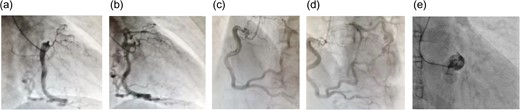

A 62-year-old woman presented with exertional chest pain. She visited our hospital because her symptoms were gradually intensifying for several years. Her only risk factor for heart disease was hypertension; she had no history of smoking, and she did not have dyslipidemia. Electrocardiography did not show any ischemic changes. On echocardiography, left ventricular function was preserved and neither hypokinesia nor valvular heart disease was observed. Further evaluation of coronary artery disease was considered necessary; therefore, she underwent a detailed examination using coronary computed tomography (CT) (Fig. 1), which revealed an LMT occlusion. Coronary angiography also revealed that the LMT was occluded at the origin. The entire left coronary artery was visualized through collateral circulation in right coronary angiography (Fig. 2). Based on blood test findings and aortic CT results, arteritis and autoimmune disease were ruled out.

(a and b) Right coronary angiography: right anterior oblique projection; (c and d) right coronary angiography: left anterior oblique projection; (e) left coronary angiography. During left coronary angiography, only the sinus of Valsalva is visualized, and there is no antegrade contrast enhancement in the left coronary artery. The left coronary artery is visualized through collateral pathways from the right coronary artery. The right coronary artery is more developed than the left coronary artery, and several collateral pathways can be observed.